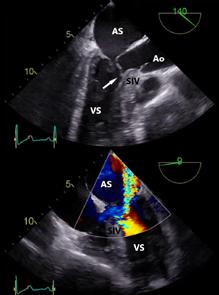

Evaluarea preoperatorie a Cardiomiopatiei Hipertrofice Obstructive

Detectarea hipertrofiei VS ce nu poate fi explicată de supraîncărcare presională ar trebui să determine continuarea investigațiilor pentru a diagnostica boala de bază. Evaluarea clinică ar trebui continuată cu efectuarea următoarelor investigații ce ar putea aduce argumente în favoarea diagnosticului de CMH: electrocardiogramă (EKG), ecocardiografie transtoracică (ETT) de repaus și de stres (dacă nu este detectat un gradient presional în tractul de ejecție al VS - TEVS), eventual ecocardiografie transesofagiană (ETE – utilă în special pentru evaluarea anomaliilor aparatului mitral), Holter EKG, rezonanță magnetică (RM) cardiacă (esențială atât pentru diagnostic cât și pentru managementul intraoperator al pacienților) și testare genetică.

Definiția CMH la adulți presupune identificarea unei grosimi a peretelui ventricular ≥15 mm în unul sau mai multe segmente ale VS, măsurătoare ce poate fi efectuată prin orice metodă imagistică, hipertrofia ventriculară neputând fi explicată doar de condițiile de umplere ventriculară.

Fig.2. Ecocardiografie transtoracică – pacient sever simptomatic cu cardiomiopatie hipertrofică. (A) Sept interventricular cu hipertrofie extremă. (B) Mișcare sistolică anterioară a valvei mitrale (SAM) și contact mitro-septal. (C) Contact mitro-septal prelungit în timpul sistolei (mod M). (D) Gradient de circa 130 mmHg în tractul de ejecție al ventriculului stâng (Doppler). Adaptat după [15]

Este esențial ca evaluările ecocardiografice să fie făcute diligent și după un protocol standard, orientarea și alinierea în planuri ortogonale trebuie să fie corecte pentru a măsura corespunzător structurile cardiace. Protocolul standard este util mai ales pentru că hipertrofia din CMH, deși interesează cel mai frecvent septul bazal, poate interesa orice segment ventricular (SIV posterior, apex VS, perete lateral)[12]. Se urmăresc parametri ca funcția sistolică și diastolică a VS, hipertrofia VS, prezența sau absența obstrucției în TEVS, volumul atriului stâng (AS), precum și date despre morfologia și funcția aparatului mitral.

Fiziopatologia care contribuie la obstrucția TEVS (Fig.2) include anomalii interconectate precum hipertrofia asimetrică a VS, SAM, hipertrofia mușchilor papilari cu sau fără deplasarea acestora, inserții anormale ale mușchilor papilari, cât și modificări la nivelul cuspelor valvei mitrale (VM)[14]

Fig.3. Ecocardiografie transesofagiană în cardiomiopatie hipertrofică obstructivă, ce remarcă obstrucția tractului de ejecție al ventriculului stâng (VS) prin contact mitro-septal (sus, săgeată) și regurgitare mitrală importantă (jos) ETE efectuată perioperator (Fig.3) este însă esențială pentru ghidarea strategiei chirurgicale în cazul miectomiei chirurgicale,

evaluarea rezultatelor acesteia și la identificarea eventualelor complicații intraoperatorii (obstrucție sau regurgitare mitrală reziduală, defect septal ventricular iatrogen, regurgitare aortică)[17]

3. Rezonanța magnetică cardiacă

RMc oferă informații despre morfologia cardiacă, funcția ventriculară și caracteristicile miocardului ventricular[18]. Evaluarea prin această tehnică a pacienților cu CMH diagnosticată sau suspectată ar trebui făcută ținând cont de recomandările ghidurilor de specialitate și ar trebui realizată și interpretată de echipe cu experiență în imagistica cardiacă și în evaluarea cardiomiopatiilor.

RMc reprezintă standardul de aur pentru cuantificarea volumelor și maselor ventriculare, fibrozei și a fracției de ejecție. Evaluarea globală și regională a funcției contractile a VS, distribuția și extensia hipertrofiei și a fibrozei, anatomia și fiziologia VM – sunt elemente cheie în stabilirea unui diagnostic cert, a prognosticului și pentru elaborarea planului terapeutic. Astfel, RMc ar trebui efectuată încă de la evaluarea inițială. Despre morfologia și funcția VS, la pacienții cu fereastră ecocardiografică bună, se pot obține informații similare prin cele două tehnici[19]. Dacă anumite segmente ventriculare sunt greu vizualizabile, cum ar fi peretele antero-lateral sau apexul VS și VD, imagistica prin RM poate aduce informațiile lipsă, necesare diagnosticului[20]

Tot imagistica radiomagnetică este utilă în evaluarea pacienților înainte de miectomia septală și poate îndruma atitudinea terapeutică deoarece poate descrie anumite caracteristici care sunt relevante pentru strategia chirurgicală, incluzând distribuția precisă a hipertrofiei septale (Fig.4), anomalii ale VM și ale aparatului subvalvular, poziționarea anormală a mușchilor papilari,

conexiuni aberante ale cordajelor, cât și anomalii ale căii de ieșire din VD. RMc poate fi folosită, utilizând proprietățile magnetice intrinseci ale țesutului miocardic și distribuția substanței de contrast pe bază de gadoliniu, pentru a detecta zonele de fibroză de la nivelul interstițiului miocardic. Captarea tardivă a gadoliniului (LGE) este utilizată pentru a diferenția miocitele normale, arhitectura acestora și ariile de fibroză. Din cauza heterogenității CMH, au fost descrise multiple modele de captare tardivă a gadoliniului: LGE subendocardică, transmurală, difuză. La 65% din pacienții cu CMH, LGE este prezentă având în mod tipic o distribuție neuniformă în zonele de hipertrofie care tind să se coreleze cu zonele de anomalii de contractilitate parietală. Fibroza este localizată mai ales în treimea medie a VS, având o distribuție multifocală, însă și VD poate fi implicat.

Extensia LGE este un marker al anomaliilor de deplasare ale pereților ventriculari și este asociată cu creșterea rigidității miocardice și cu remodelarea ventriculară avansată. Aprecierea gradului de fibroză septală prin identificarea LGE, poate fi utilă în alegerea conduitei terapeutice, înaintea tratamentului invaziv al înlăturării obstrucției din TEVS[24]

Fig.4. Cuantificarea exactă a distribuției și dimensiunilor hipertrofiei septale în diferite secțiuni de rezonanță magnetică cardiacă.